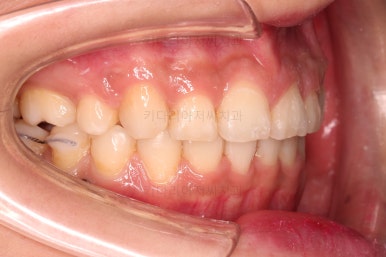

1. 초진

연산동교정치과 초진 시 입안의 모습입니다.

얼핏 앞에서 봤을 때 치열이 나쁘지 않아 보이는데요.

대신 자세히 살펴보면 윗니 양쪽 송곳니가 덧니처럼 볼록 튀어나와 있고요.

아랫니 어금니가 하나 없어서 주위 치아들이 해당 위치로 쓰러진 상태였습니다.

그리고 양쪽의 교합이 톱니바퀴처럼 맞물려 있는 것 같지만 톱니바퀴가 한 칸씩 밀려서 맞물려 있는 부정교합이 있는 상태였습니다.